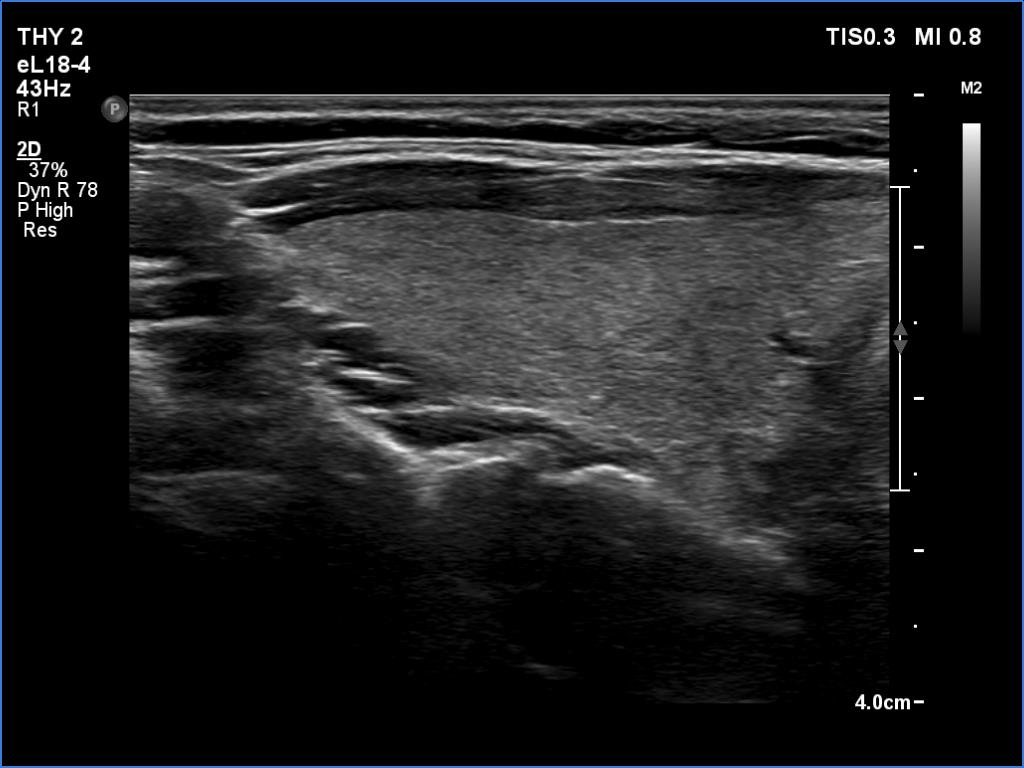

Follow-up examination five years later (ultrasonographic picture 2)

Right lobe, longitudinal scan.